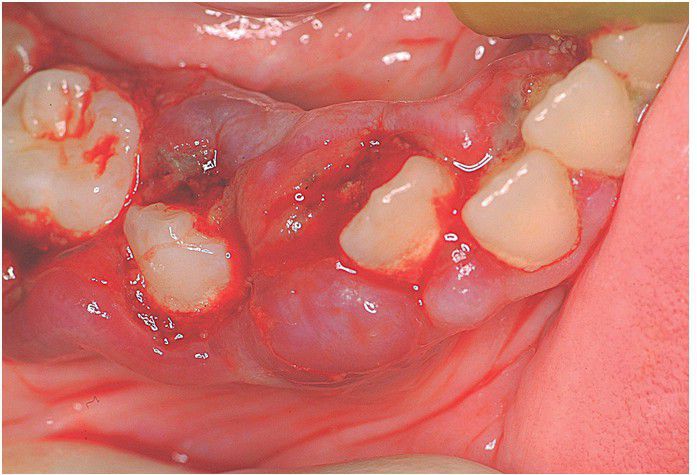

Scurvy

Hemorrhagic gingival enlargement (scorbutic gingivitis) because of capillary fragility.